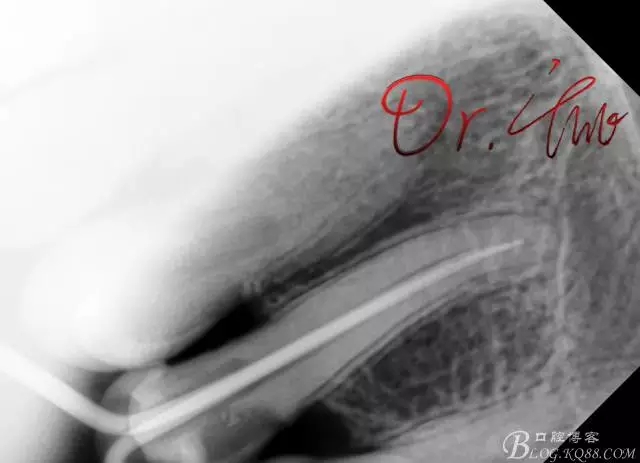

初診照

640.webp.jpg